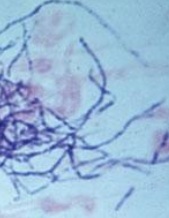

Actinomyces odontolyticus, gram positive bacteria that grow best under low or no oxygen conditions, have been isolated in female genital tract specimens from 4.8% of women fitted with intrauterine contraceptive devices, in 4% of women with pelvic inflammatory disease, and in 1.8% of women without pelvic inflammatory disease. Because of their poor growth in the presence of oxygen it can be hard to culture or grow them from wounds i.e. you can be infected by them with cultures that show no bacterial growth. Culture requires immediate specimen transport and prolonged anaerobic incubation. They are soil and water saprophytes that live off decaying organic matter and grow in unbranched or branched filaments of cells the way mold grows.

They form hard lumps in infected tissue that soften as they extend through the soft tissue forming multiple draining abscesses containing yellow colored granules composed of actinomyces microcolonies, cellular debris and associated microorganisms. These small granules may be seen as small masses on CT or MRI scans. In advanced cases they can destroy bone.

Actinomycosis infections are endogenous infections from mucous membranes i.e. you infect yourself. Since they live off decaying matter the combination of blood and injected fat is a perfect environment for them as some of the injected or grafted fat as in a Brazilian buttock lift is dying while awaiting for the ingrowth of blood vessels. When specimens are tested for their presence they are placed on blood agar gels because actinomyces thrive on blood. I am aware of one case where the actinomyces from an old IUD infected the buttocks after fat grafting – Brazilian buttock lift. After more than 6 months of treatment with multiple hospitalizations and operations that patient was left with deformed buttocks. Because the bacteria live off of dead tissue in areas of low oxygen and blood flow they can require 12 to 18 months of antibiotic treatment to clear.